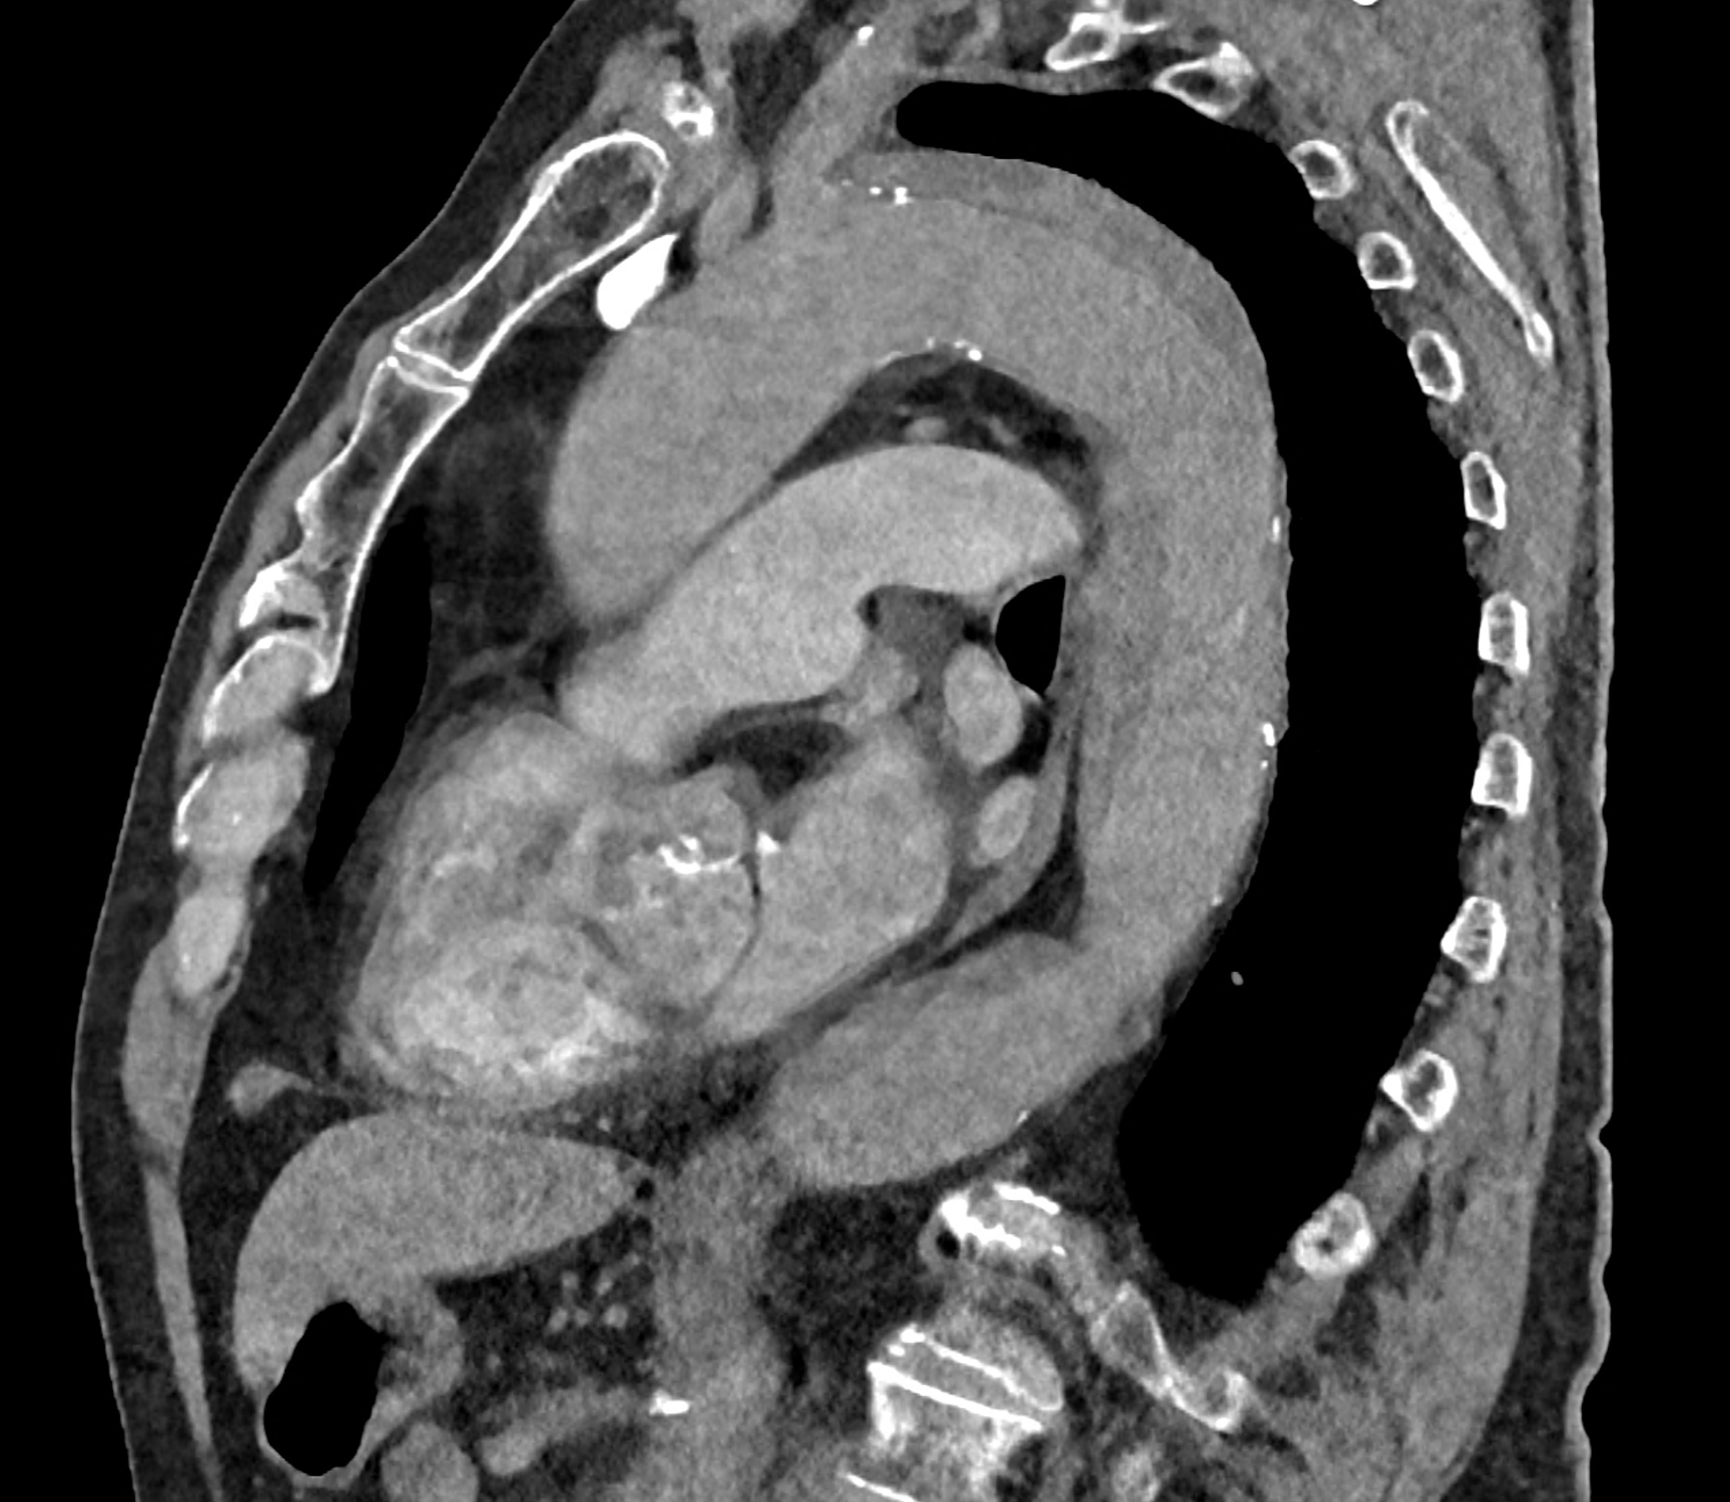

in patient chest pain, negative ECG but with elevated D-dimers was performed CTA of the chest to exclude highly suspected pulmonary embolism. No pulmonary embolism was see, but the pathology of the aortic arch and descending thoracic atorta. The images were consistent with aortic intramural hematoma type B according to the Stanford classification with incipient transformation in dissection – behind the subclavian artery, it is clear that the contrast agent is flowing into the intramural hematoma. Differentiation from wall thrombosis is facilitated by the presence of calcification in the detached intima, which is most clearly visible on virtual non-contrast imaging. The intramural hematoma itself exhibits different properties in terms of X-ray absorption. Coagulated blood is visible at the apex of the aortic arch, where it closely adjoins the area that is perfused and filled with contrast medium. There are other smaller areas filled with contrast medium at the sites of the intercostal arteries. These areas are secondary sites where the original intramural hematoma is channeled during its transformation into a classic aortic dissection.

Virtual non-contrast images help to distinguish between the intima and thus in the differential diagnosis of intramural hematoma versus wall thrombosis. Signs of fresh coagulated blood in IMH indicate bleeding into the aortic wall from the vasa vasorum. In contrast, monoenergetic images with lower energies of 40-55 keV highlight areas of intramural hematoma with active blood flow.

comparison of the sagittal aortic MPR in 40, 60, 140 and 190 keV monoenergetic images

comparison of the perpendicular planes to sagittal aortic MPR in 40, 60, 140 and 190 keV monoenergetic images